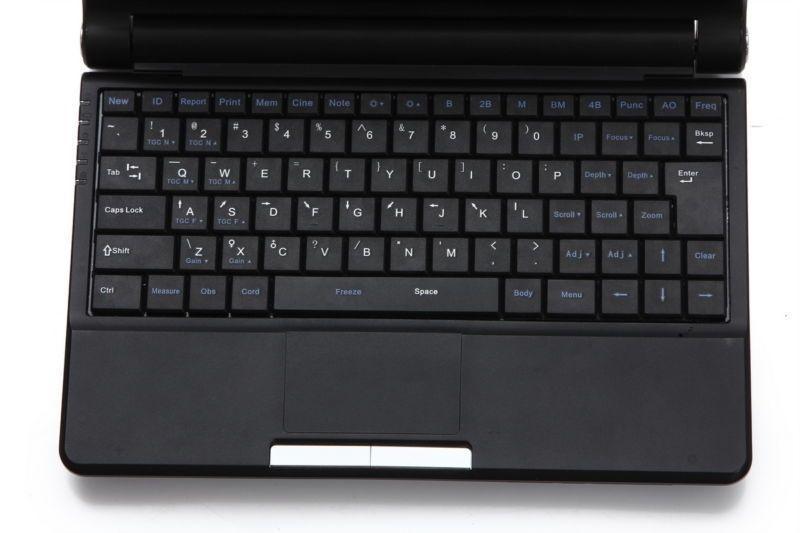

User-Friendly Interface

One of the standout features of this laptop ultrasound scanner is its user-friendly interface. The software is designed to be intuitive, which means that even those new to using ultrasound machines can quickly grasp the necessary functions. This accessibility is crucial in a fast-paced medical environment, where time matters. Additionally, the device supports 3D imaging, providing practitioners with a comprehensive view of the anatomy, thus enhancing the accuracy of their assessments.